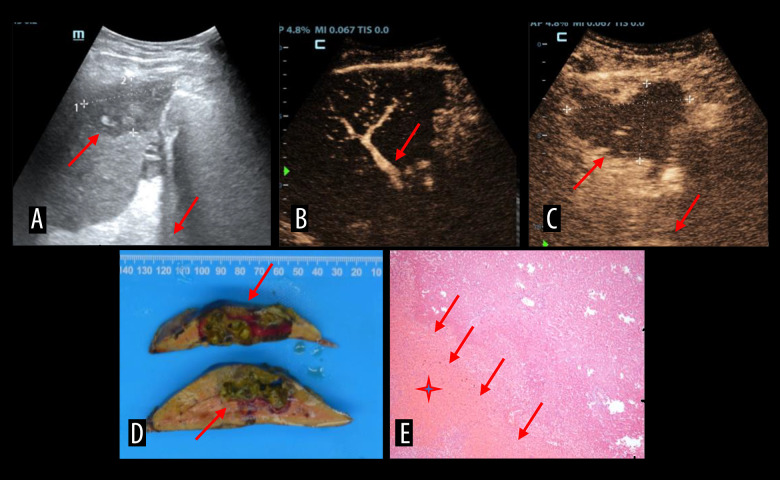

肝动脉血栓形成是肝移植术后最常见、最严重的血管并发症。经导管动脉溶栓具有高选择性、低剂量、局部药物浓度高、对全身凝血功能影响小等优点。动脉内对比增强超声(IA-CEUS)无辐射,可重复,可在床边进行,可作为连续监测的替代方法。我们描述了IA-CEUS在评估连续经导管动脉溶栓治疗肝移植后肝动脉血栓形成的效果中的有效性。材料与方法选取2016年11月至2023年5月肝移植术后诊断为肝动脉血栓形成的患者8例。所有8例患者均采用尿激酶连续经导管动脉溶栓。在溶栓治疗期间,对每位患者进行IA-CEUS动态监测。采用肝动脉数字减影血管造影对结果进行验证。结果2例患者出现肝动脉灌注缺损。6例患者动脉灌注良好。3例患者出现胆囊瘤。一名患者患上了夹层动脉瘤。一名患者出现假性动脉瘤,导管移位。1例患者出现腹膜后血肿。所有患者均未出现造影剂相关并发症。结论IA-CEUS作为评价经导管动脉溶栓治疗肝移植术后肝动脉血栓疗效的新选择是安全可行的。

BACKGROUND Hepatic artery thrombosis is the most common and severe vascular complication after liver transplantations. Transcatheter arterial thrombolysis is a viable alternative with high selectivity, low drug dosage, high local drug concentration, and minimal effect on systemic coagulation function. Intra-arterial contrast-enhanced ultrasound (IA-CEUS) is radiation-free and repeatable, can be performed bedside, and could be an alternative for continuous monitoring. We described the efficacy of IA-CEUS in assessing the effect of continuous transcatheter arterial thrombolysis in post-liver transplant hepatic artery thrombosis in a series of cases. MATERIAL AND METHODS Eight patients with diagnosis of hepatic artery thrombosis after liver transplantation between November 2016 and May 2023 were selected. All 8 patients underwent continuous transcatheter arterial thrombolysis, using urokinase. Dynamic IA-CEUS monitoring was performed for each patient during the thrombolysis treatment. Hepatic artery digital subtraction angiography was used to verify the results. RESULTS Two patients showed a hepatic artery perfusion defect. Six patients demonstrated good perfusion of artery. Three patients developed biloma. One patient developed a dissection aneurysm. One patient developed a pseudoaneurysm with catheter displacement in it. One patient developed retroperitoneal hematoma. None of the patients experienced contrast agent-related complications. CONCLUSIONS IA-CEUS was found to be safe and feasible as a new option for evaluating the efficacy of transcatheter arterial thrombolysis in post-liver transplant hepatic artery thrombosis.